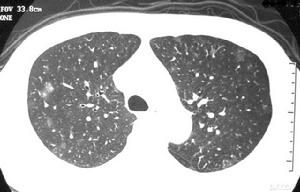

卡肺囊蟲肺炎2.兒童-成人型(現代型)起病較急,開始時乾咳,迅速出現高熱、氣促、發紺,肺部體徵甚少,可有肝脾腫大。從起病到診斷,典型的為1~2周,接受大劑量激素治療者,病程短促,可於4~8天死亡。AIDS患者病程較為緩慢,漸進,先有體重下降、盜汗,淋巴結腫大,全身不適,繼而出現上述呼吸道症狀,可持續數周至數月。未經治療100%死於呼吸衰竭。本病症狀嚴重,但肺部體徵較少,多數患者肺部聽診無異常,部分病人可聞及散在濕囉音。

卡肺囊蟲肺炎2.血氣和肺功能動脈血氣常有低氧血症和呼吸性鹼中毒。肺功能檢查肺活量減低。肺彌散功能(DLCO)低於70%估計值。